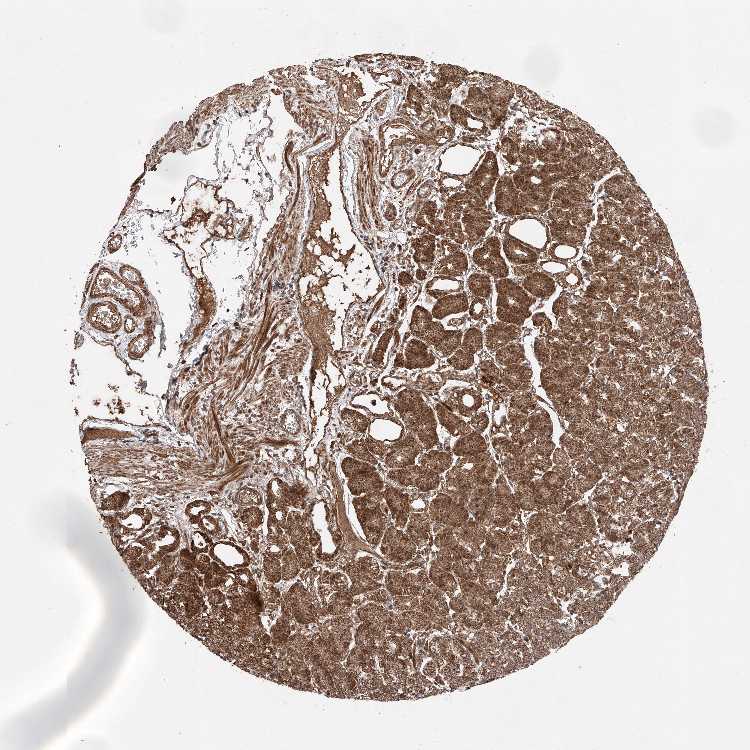

TISSUE PRIMARY DATA STOMACH Show tissue menu

STOMACH 1 - Antibody stainingi

Antibody staining in the annotated cell types in the current human tissue is reported as not detected, low, medium, or high, based on conventional immunohistochemistry profiling in selected tissues. This score is based on the combination of the staining intensity and fraction of stained cells.

Each image is clickable and will lead to virtual microscopy that enables deeper exploration of all samples and also displays staining intensity scores, fraction scores and subcellular localization as well as patient and tissue information for each sample.

Antibody HPA007241Antibody HPA011109

Glandular cells HighHigh